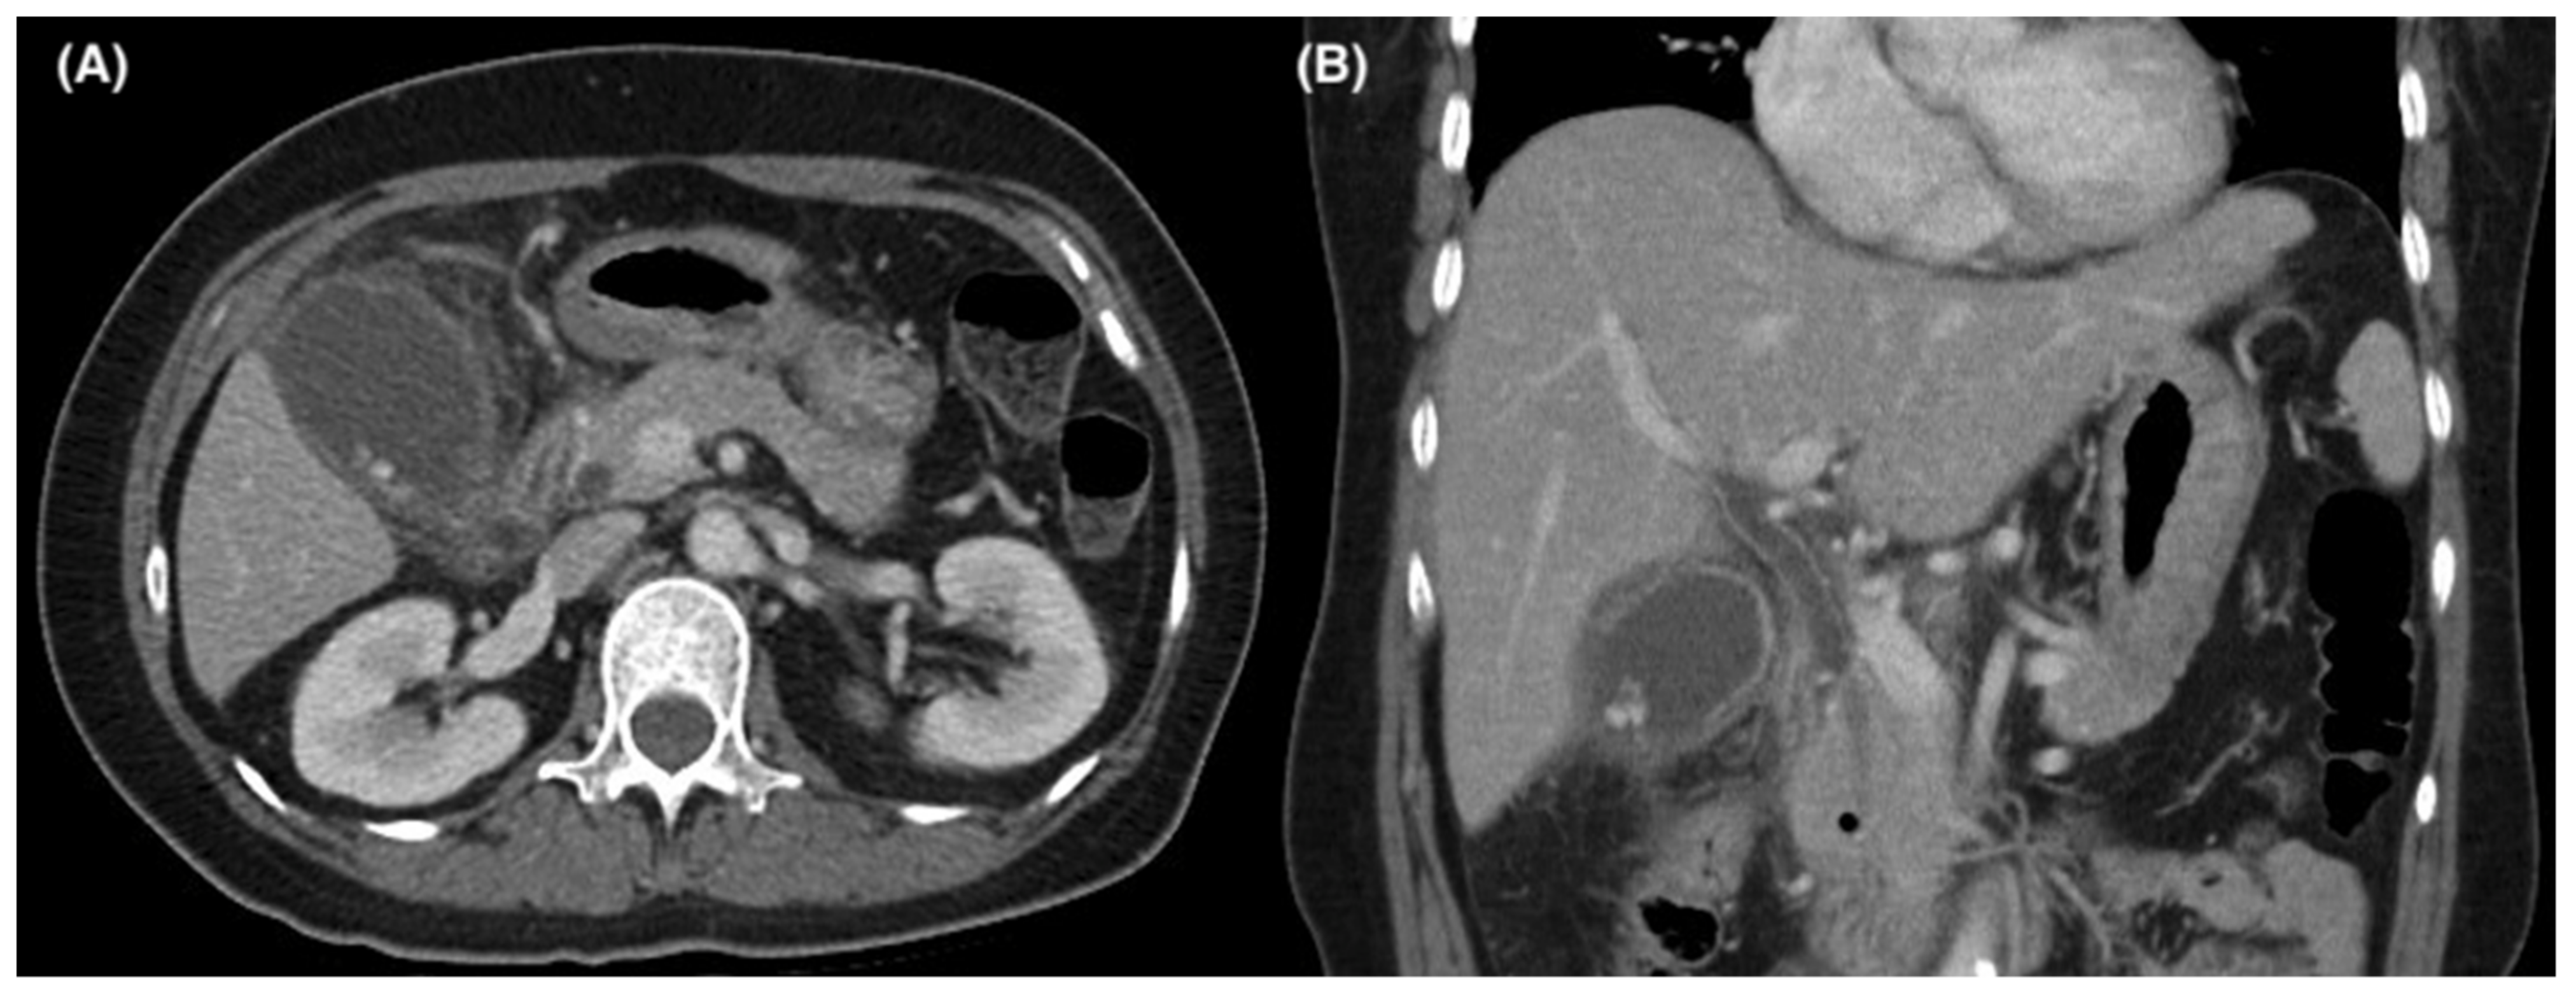

Figure 1.

Axial (A) and coronal (B) computed tomography images of a patient with concurrent acute cholecystitis and cholangitis.